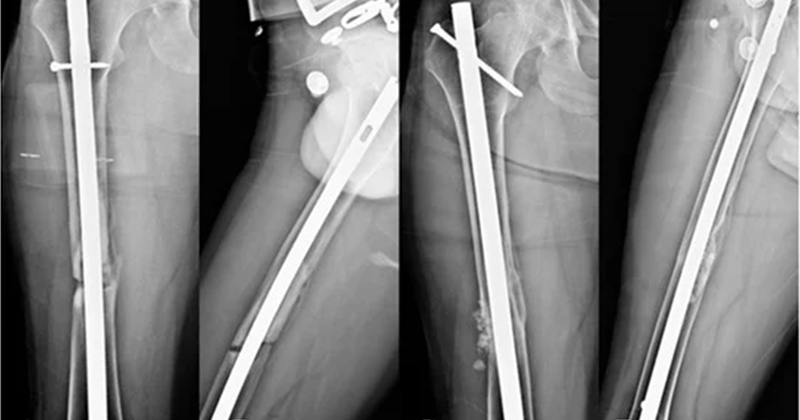

Intramedullary nailing involves inserting a metal rod into the central canal of a long bone, such as the femur, tibia, or humerus. This rod spans the length of the fracture and is secured with locking screws at both ends to maintain stability. Nailing is particularly effective for shaft fractures, as it provides strong internal support while allowing early weight-bearing and faster rehabilitation. Because the implant is placed inside the bone, it preserves surrounding soft tissues and blood supply, promoting efficient healing.

Plating, on the other hand, involves attaching a metal plate along the surface of the fractured bone using screws. This method is commonly used for fractures near joints or in areas where precise anatomical reconstruction is required, such as the wrist, ankle, or clavicle. Plating allows direct visualization of the fracture, enabling accurate alignment and fixation. Modern locking plates provide enhanced stability, especially in osteoporotic or comminuted fractures.